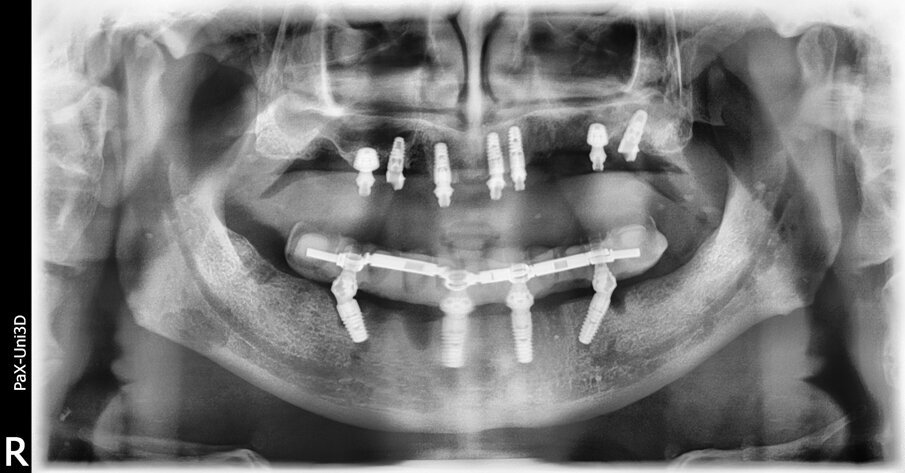

(Fig. 5). Allo scopo di ottimizzarne il livello di stabilità primaria, particolare attenzione viene posta nella ricerca di un bi-corticalismo creando una frattura a legno verde, mediante l’utilizzo di osteotomi di Summers, del pavimento del seno mascellare e ingaggiando la corticale del pavimento con le prime spire dell’impianto. Nessuna procedura di rialzo sinusale è stata eseguita e non si è determinata alcuna protrusione dell’impianto all’interno dei seni mascellari. Tutti gli impianti sono stati collocati con un torque di inserimento pari o superiore a 35 Ncm. Il controllo radiografico, eseguito mediate esame ortopanoramico, evidenzia il corretto inserimento gli impianti (Fig. 6).

Fig. 6_L’ortopanoramica immediata post-operatoria mostra gli impianti in una buona posizione. Gli impianti ultra-short sono ben inseriti in rapporto ai seni mascellari, seppur circondati da una scarsa quantità di osso.

Il follow up è stato programmato con cadenza semestrale. Al momento della produzione di questo articolo, il caso è stato seguito per 18 mesi. Nell’arco di questo periodo è stata segnalata solo una complicanza di minore entità. La rottura di un angolo incisale dell’incisivo centrale, che è stata riparata direttamente alla poltrona. Dopo 18 mesi, l’ortopanoramica di controllo evidenzia una perfetta stabilità e, anzi, un miglioramento dei livelli ossei perimplantari. In particolare, a livello degli impianti ultra-short è possibile apprezzare una migliore densità ossea circonferenzialmente all’impianto e persino nella sua porzione più coronale, come è possibile apprezzare confrontando l’ortopanoramica eseguita immediatamente dopo l’intervento con quella a 18 mesi (Figg. 11a, 11b).

Fig. 11a_Ortopanoramica a 18 mesi. Appare evidente l’incremento della densità ossea intorno agli impianti, in particolare di quelli ultra-short.

Fig. 11b_Confronto della qualità ossea prima e dopo 18 mesi degli impianti ultra-short inseriti a livello del mascellare superiore destro e sinistro.